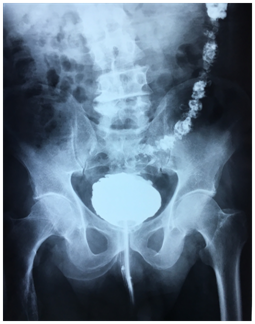

An antibiotherapy was started and retrograde and urinary uretro-cystography was performed. Retrograde cystography showed diverticular bladder with opacification of the sigmoid colon up to the half of the transverse colon (Figure 1) (Figure 2).

Figure 1 Frontal view of retrograde urethrocystography showing opacification of the sigmoid and descending colon.

Usually, Because of high pressure in the intestine, the fistula works from the intestine to the bladder except when there is an obstacle on the lower urinary tract, as was the case of our patient resulting in opacification of the intestine during cystography thus permitting diagnosis of entro-vesical fistula.